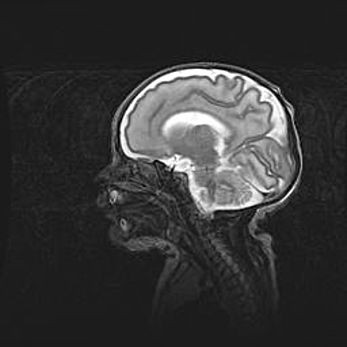

Аномалия Денди-Уокера. Признаки гипоплазии мозолистого тела.

Возраст: 5 месяцев 3 дня

Вес: 5550 г

Пол: мужской

Окружность головы: 39 см

Срок гестации: 40 недель

Аномалия Денди-Уокера – это порок развития головного мозга, для которого характерна триада симптомов: гипотрофия или аплазия червя мозжечка и/или полушарий мозжечка, расширение четвёртого желудочка с формированием ликворной кисты задней черепной ямки, гипертензионная гидроцефалия различной степени.

Гипоплазия мозолистого тела относится к дефектам внутриутробного этапа развития мозговой ткани, возникающим в процессе закладки структур головного мозга, что происходит на начальных этапах развития эмбриона.